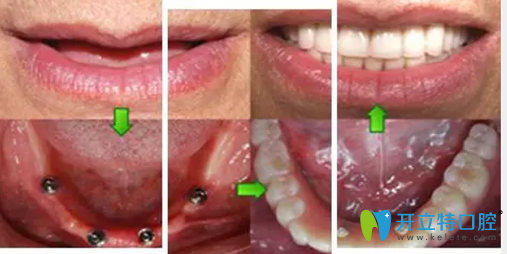

種植需要避開手術(shù)后的骨缺失區(qū),所以對種植體的承受力和穩(wěn)定性要求較高,同時(shí)郭先生對美觀要求較高。萬院長根據(jù)郭先生的需求與口腔情況后為他進(jìn)行了植骨手術(shù),傷口愈合后,萬院長為他進(jìn)行CT掃描后確認(rèn)可以進(jìn)行種植牙手術(shù)。

萬書健院長給郭先生推薦的是“All-on-4種植牙”,它是利用4顆種植體,1次完成口腔種植修復(fù),一番詳細(xì)交流之后,當(dāng)天就決定種牙。萬院長一邊在電腦上給他演示種牙的位置、顆數(shù),一邊給他分析這樣設(shè)計(jì)的優(yōu)勢和好處。

All-on-4種植牙種植過程圖:

術(shù)后結(jié)束后,郭先生看著整齊的牙齒,笑得合不攏嘴,他說,有了牙,我就有了好胃口,胃口好了,我就能安心享受晚年的生活啦!